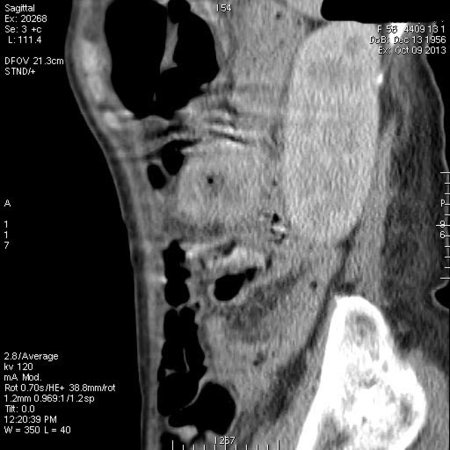

Женщина средних лет поступила в хирургическое отделение с кишечным кровотечением.

Пальпируется образование в мезогастриуме слева. При УЗИ определяется тумор, не связанный с толстой кишкой.

КТ

Операция - обнаружена опухоль тонкой кишки, предположительно гемангиома, выполнена резекция части кишки.

Гистологический ответ - GIST.

GIST тонкой кишки